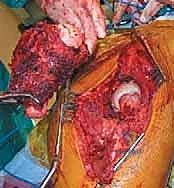

الخطوة 2: استئصال الورم ورأس الفخذ المتضرر

يتم خلع رأس الفخذ من الحُق. ثم يقوم الجراح بقطع عنق الفخذ وإزالة رأس الفخذ المصاب بالسرطان بالكامل. يتم تنظيف المنطقة المحيطة بعناية فائقة وإزالة أي أنسجة ورمية هشة (Curettage) للوصول إلى عظم صحي وقوي قدر الإمكان.

الخطوة 3: إعادة بناء تجويف الحُق (Acetabular Reconstruction)

إذا كان الورم قد دمر تجويف الحوض، فإن هذه المرحلة تتطلب مهارة هندسية حيوية.

* يتم تنظيف التجويف وتوسيعه بآلات خاصة.

* إذا كان التدمير كبيراً، يستخدم الدكتور هطيف دعامات معدنية خاصة (Reconstruction Rings/Cages) يتم تثبيتها بمسامير في عظام الحوض السليمة لإنشاء سقف جديد للمفصل.

* يتم تثبيت الكوب البلاستيكي أو المعدني (Socket) باستخدام الأسمنت العظمي لضمان ثباته الفوري.